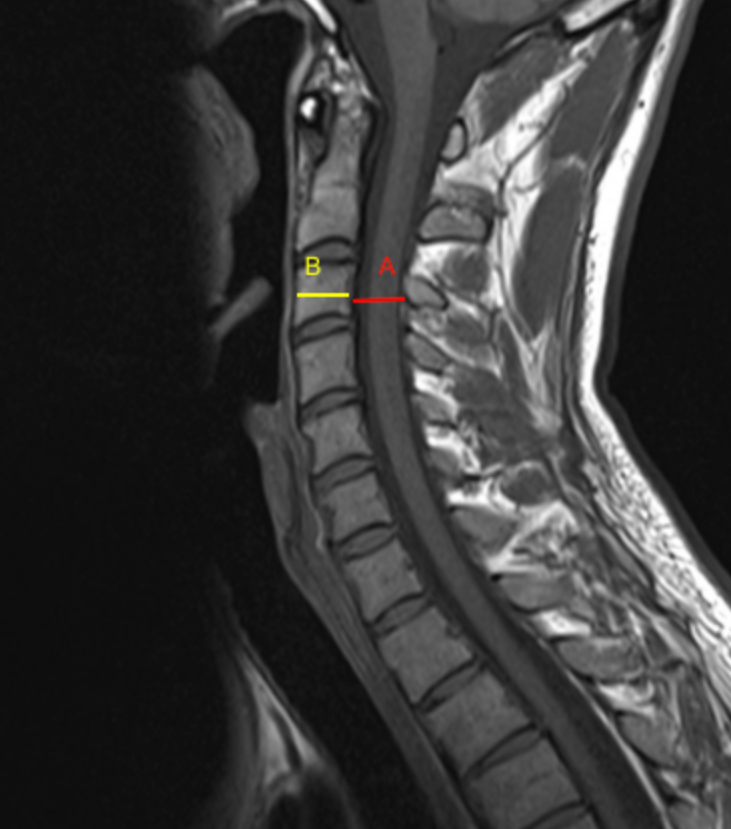

The Pavlov–Torg ratio, also known as the canal–body ratio, is a dimensionless measurement used to assess cervical spinal canal stenosis by comparing the sagittal diameter of the spinal canal to the sagittal diameter of the corresponding vertebral body at the same level.

• Measure the Sagittal Canal Diameter (A):

• Measure the shortest anteroposterior distance between:

• The posterior margin of the vertebral body or disc–osteophyte complex (anterior canal boundary), and

• The anterior margin of the ligamentum flavum or lamina (posterior canal boundary).

• Measure the Sagittal Vertebral Body Diameter (B):

• Measure the anteroposterior diameter of the vertebral body at the same level, from the anterior cortex to the posterior cortex of the vertebral body.

• Calculate the Pavlov–Torg Ratio:

Pavlov-Torg Ratio = AB